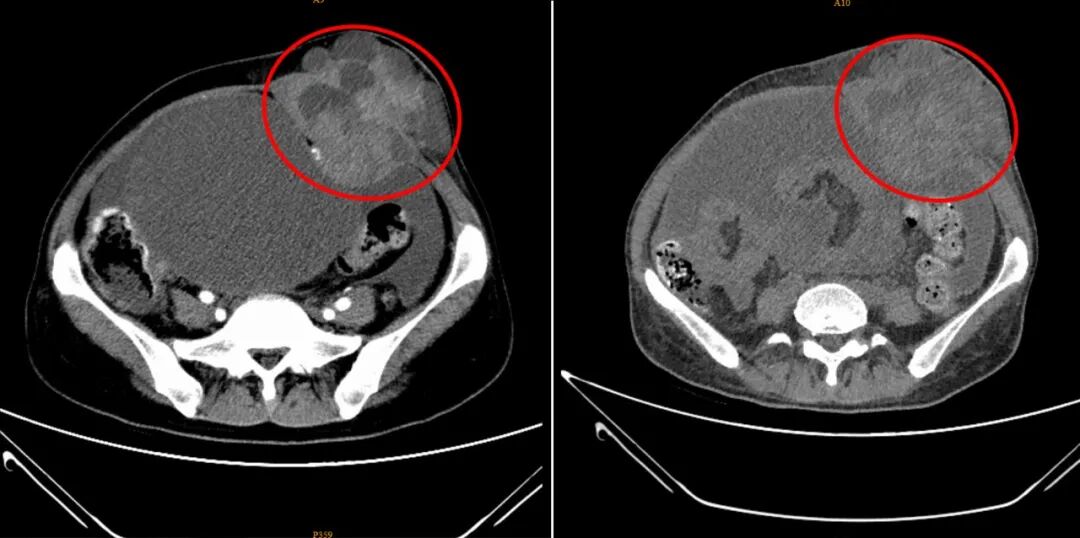

孙女士在深圳华侨医院治疗短短一个月的前后对比CT影像图。病灶部位呈现出体积显著缩小、边界趋于清晰、内部密度更加均匀的积极变化,表明治疗已取得明显成效。